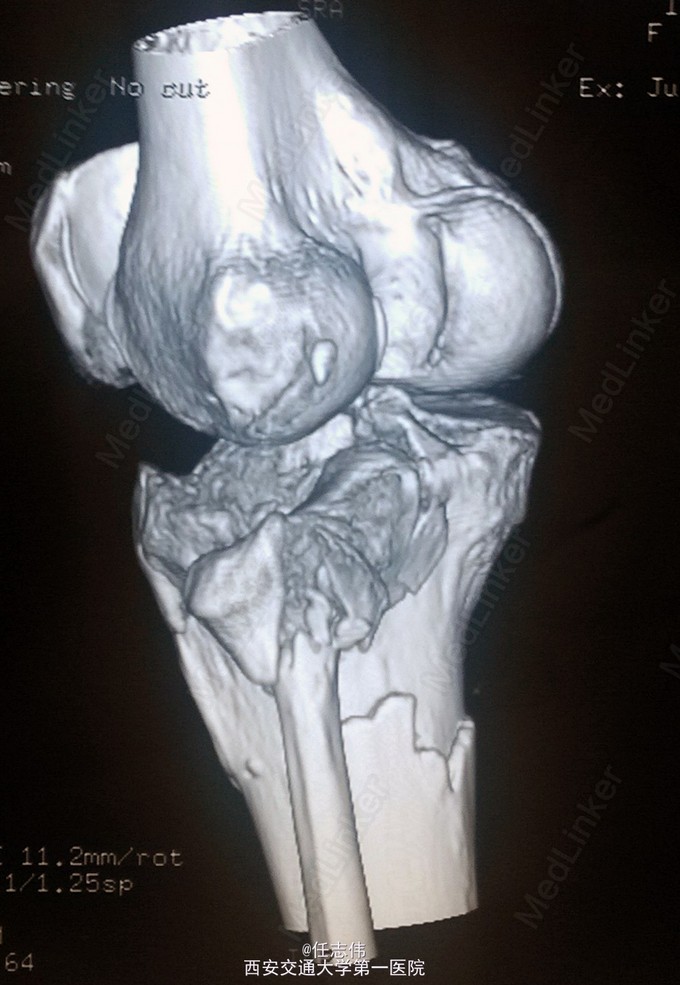

女性,66岁,摔伤致左膝部疼痛活动受限7天 7天前摔伤致左膝部疼痛伴活动受限,在当地医院行跟骨牵引、消肿对症治疗7天,已基本消肿,足部感觉、活动、血供正常。 既往有糖尿病史。

左膝关节周围肿胀,胫骨平台处压痛明显,外侧为著,膝关节活动受限。左足背动脉搏动好,踝及足趾感觉活动正常。

诊断:右胫骨平台骨折 处理:骨折切开复位内固定术。行内外侧入路钢板固定,术中行外侧平台塌陷复位,髂骨植骨内固定。另因考虑有后柱骨折,遂行后外侧切口,支撑钢板固定。术中见患者骨质疏松明显。 术后伤口愈合好,局部仍肿胀明显。

有几个问题想问问: 1.这个是胫骨平台骨折吗?还是胫骨近端骨折伴有平台骨折。 2.手术处理上有什么建议?可以不处理后侧柱吗? 3.大家在复位塌陷平台上有和经验?